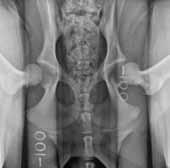

Canine hip dysplasia, or CHD, is defined by the radiographic presence of hip joint laxity or osteoarthritis with hip subluxation (laxity) early in life. A developmental disease of complex inheritance it is the most common orthopedic disease in large- and giant-breed dogs and causes pain and loss of mobility.

Currently, there are two screening methods used by breeders in the US: the Orthopedic Foundation of Animals (OFA) method, and the PennHIP method.

The traditional OFA screening method relies on conventional hip-extended (HE) radiographs, which Dr. Smith argues do not provide critical information needed to accurately assess passive hip joint laxity and therefore osteoarthritis susceptibility.

“We believe the insensitivity of the OFA method for detecting hip joint laxity is not the fault of the expert

radiologist interpreting the HE radiograph, but rather an inherent deficiency of the HE radiographic view,” said Dr. Smith.

In order to achieve genetic control of CHD and create a system that would have more accurate diagnostic outcomes, Dr. Smith developed the PennHIP method as a more effective way to evaluate whether a dog will develop canine hip dysplasia in its lifetime. His method has gone head-to-head with the traditional OFA hip-screening method, which was developed in the early 1960s.

Most recently, Dr. Smith offered a comparison of the PennHIP method against the OFA method in the September 2010 issue of the Journal of the American Veterinary Medical Association (JAVMA), where he illustrated that the PennHIP method called for more stringent breeding practices in order to lessen the prevalence of CHD.

PENNHIP VS. OFA

The PennHIP method quantifies hip laxity using the distraction index, or DI, metric, which ranges from a low of 0.08 to greater than 1.5.

Smaller numbers mean healthier hips.

The PennHIP DI has been shown in several studies at multiple institutions to be closely associated with the risk of osteoarthritis and canine hip dysplasia. It can be measured as early as 16 weeks of age without harm to the puppy.

The OFA grades hip joints in dogs in seven categories: excellent, good, fair, borderline, mild, moderate and severe hip dysplasia. The scoring system is a pass/fail one.

The PennHIP method is not pass/fail, but rather it quantifies on a continuous scale the “risk” of a dog acquiring OA. It considers a DI of less than 0.3 to be the threshold below which there is a near-zero risk of developing hip osteoarthritis later in life. In contrast, dogs having hip laxity with DI higher than 0.3 show increasing risk of developing hip osteoarthritis earlier and more severely, as the DI increases.

Comparing the overall results of the study, 52 percent of dogs OFA-rated “excellent,” 82 percent of dogs OFA-rated “good” and 94 percent of dogs OFA-rated “fair” fell above the PennHIP threshold of 0.3, making them all susceptible to the osteoarthritis of CHD though scored as “normal” by the OFA. Of the dogs the OFA scored as “dysplastic” all had hip laxity above the PennHIP threshold of 0.3, meaning there was agreement between the two methods on dogs showing CHD or the susceptibility to CHD.

The key feature of the PennHIP radiographic method is its ability to determine which dogs may be susceptible to osteoarthritis later in life. Because dogs are recognized as excellent models for hip osteoarthritis in humans, Dr. Smith’s PennHIP technology may be a viable option for human medicine.